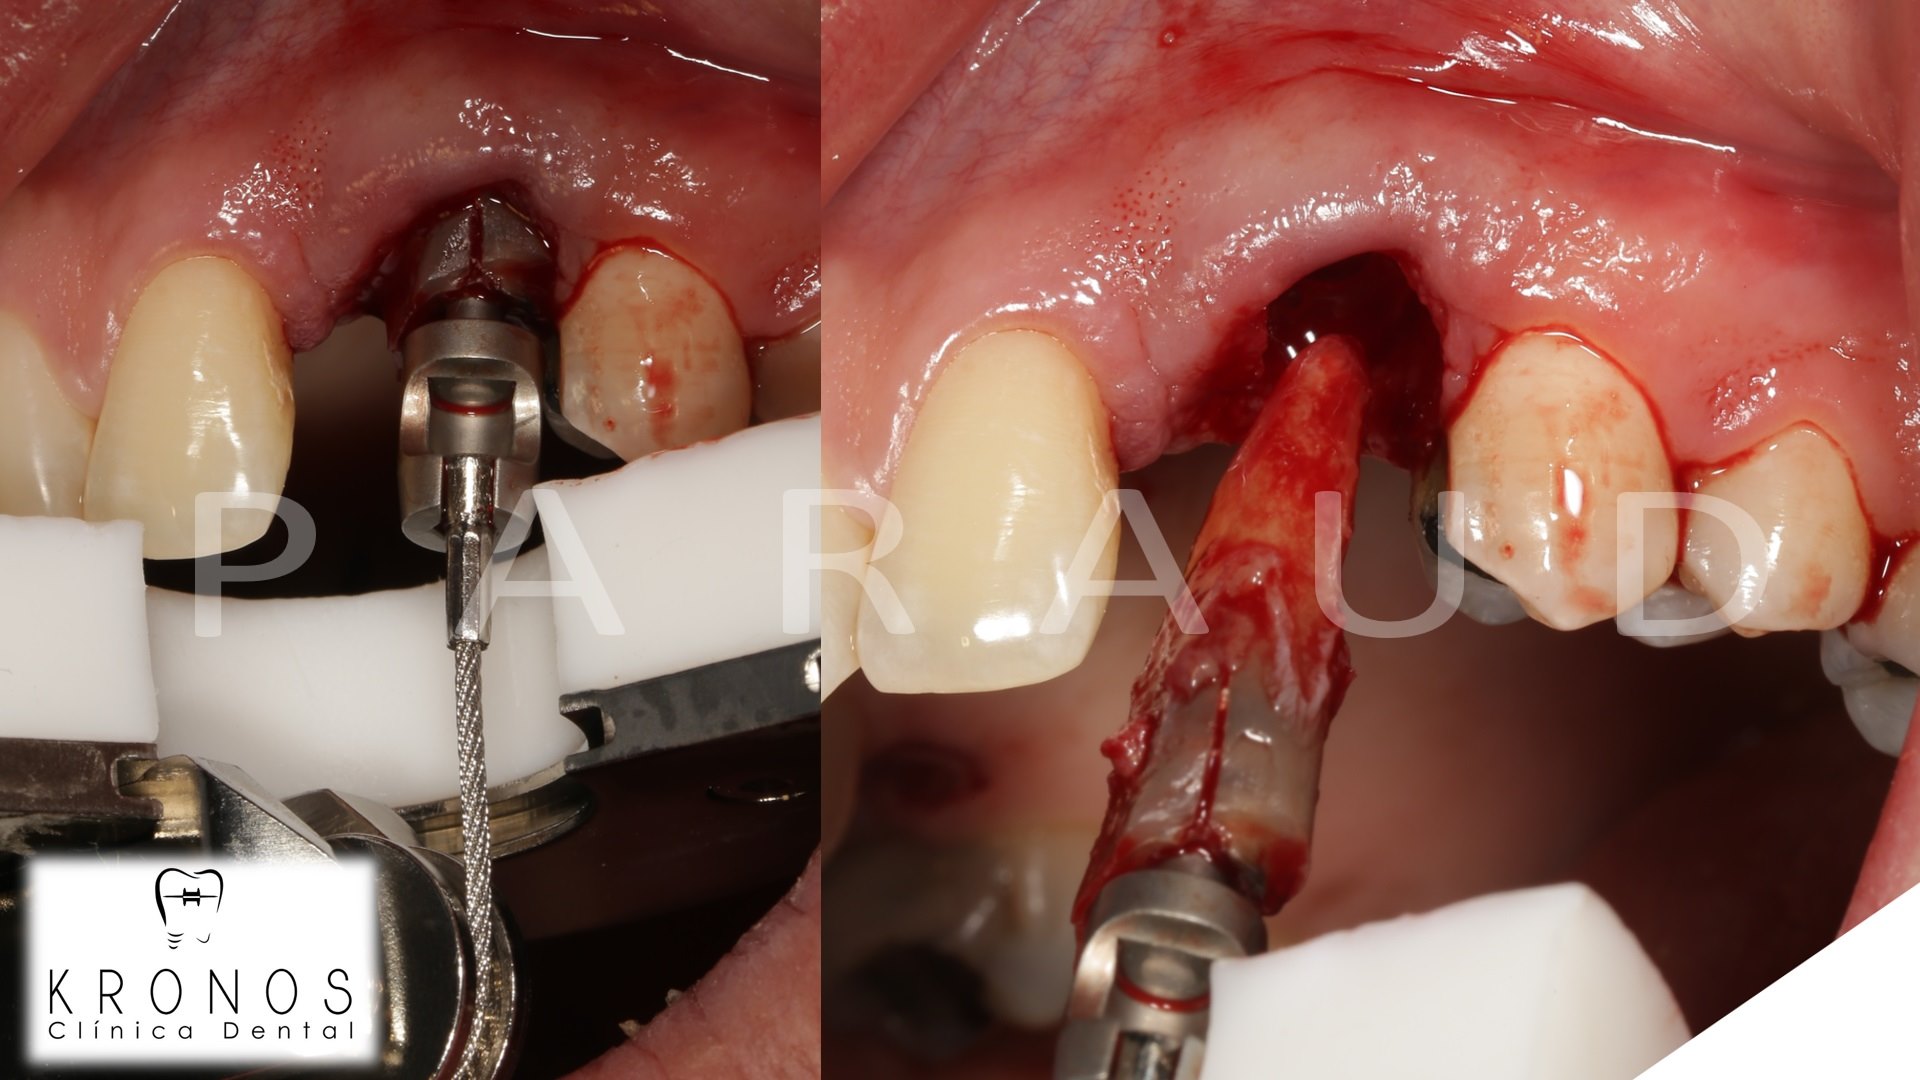

Clinical case: Extraction, immediate implant placement, & provisionalization

- Courtesy of Dr. Iulian Filipov, Romania -

AnyRidge, R2GATE, guided surgery, immediate placement, immediate provisionalization, initial stability, Dr. Iulian Filipov, #25, maxillary posterior, immediate loading, Mega ISQ

AnyRidge implant system, R2GATE, MEGA ISQ, Digital prosthesis